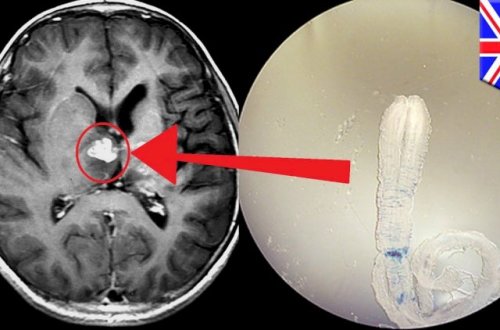

Başınızda bu əlamətlər varsa, deməli beyninizdə qurd var

473

zaman

keçir

kistlər

çirkli

beyinə

gigiyenaya

olduqda

verir

xəstəlik

yoluxma

beyin

çevrilir

yumurtaları

xəstə

parazitin

insan

parazitar

Əgər

olaraq

Çistiçerkoz